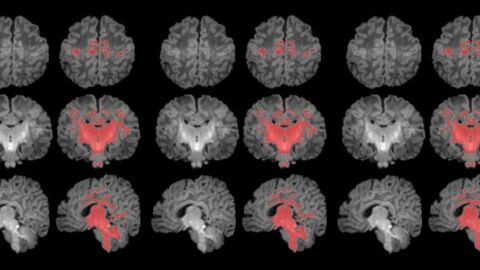

La exposición prenatal a la contaminación del aire se relaciona con una maduración más lenta del cerebro durante el primer mes de vida. Así lo ha revelado el primer estudio que mide con resonancia magnética la mielinización cerebral de los recién nacidos.

La mielinización es un proceso clave en la maduración del cerebro, en que la mielina recubre las conexiones neuronales y las hace eficientes para la transmisión de información. Los recién nacidos de madres expuestas a niveles más altos de partículas finas en suspensión durante el embarazo muestran una mielinización más lenta en esta etapa tan precoz de la vida.

Los resultados muestran una correlación clara entre una mayor exposición materna a PM2.5 durante el embarazo y una menor mielinización en el cerebro de los recién nacidos.